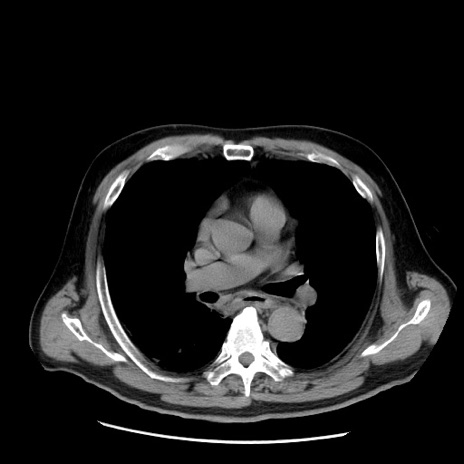

症例20(横断像)

【症例】 60歳代男性

【主訴】 腹部膨満、嘔吐

【現病歴】5日前頃より倦怠感を認め食事量減少し4日前の朝嘔吐、食事摂取困難となった。 3日前近医受診し点滴施行され整腸剤などを処方された。 当日他院を受診し、腹部膨満著明、炎症反応の上昇(CRP10.8、WBC11200)あり、紹介受診となる。

【身体所見】 意識JCS1 受け答えがはっきりしないBP 111/57mHg、 P 67bpm、、BT35.2°C、SpO2 97%(RA)、 腹部:膨隆、打診で鼓音あり、全体的に圧痛有り、腸蠕動音(-)、反跳痛ははっきりせず。

【データ】WBC 11400、CRP 14.20